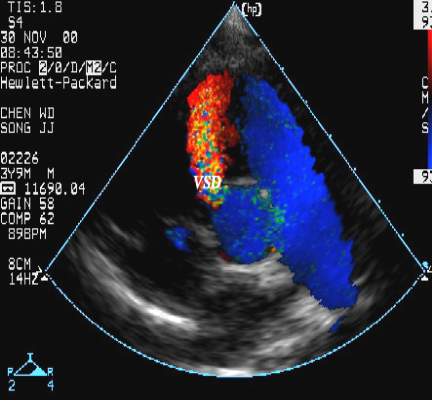

室间隔缺损:超声心动图表现

室间隔缺损(流入道部)